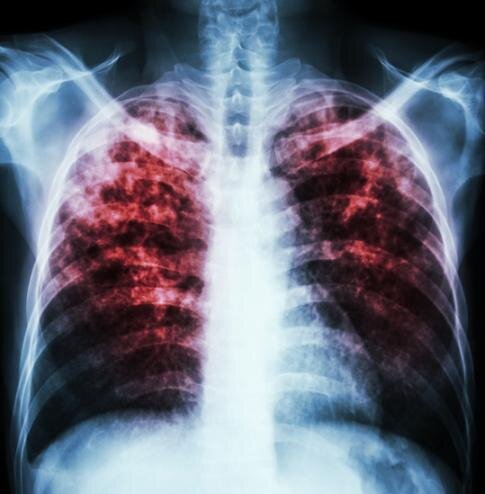

میزان مرگومیر و بروز سل در سطح جهان از زمان همهگیری کووید افزایش یافته و سل را بهعنوان کشندهترین قاتل عفونی در صدر قرار داده است.

۱.۶ میلیون نفر در سال ۲۰۲۱ بر اثر سل جان خود را از دست دادند. سوءتغذیه مهمترین عامل ابتلا به سل است و این در مطالعات بسیاری از کشورها، ازجمله آفریقای جنوبی نشان داده شده است، جایی که محققان سطوح ضعیفی از تغذیه را در بیماران بستری شده در بیمارستان تخصصی سل دریافتند.

سوءتغذیه به تمام اشکال کمبودهای تغذیه ازجمله تغذیه بیش از حد و چاقی و بهطور خاص به کمبود مواد مغذی اشاره دارد. بسیاری از بیماران مبتلا به سل تغذیه نامناسبی دارند و آخرین شواهد نشان میدهد که سوءتغذیه نیز نقش کلیدی در ابتلا به سل در خانوادهها دارد.

نتایج کارآزمایی نشان میدهد که بهبود تغذیه در اعضای خانواده بیماران مبتلا به سل ریه تقریبا ۴۰ درصد باعث کاهش همه اشکال سل و نزدیک به ۵۰ درصد سل عفونی میشود.